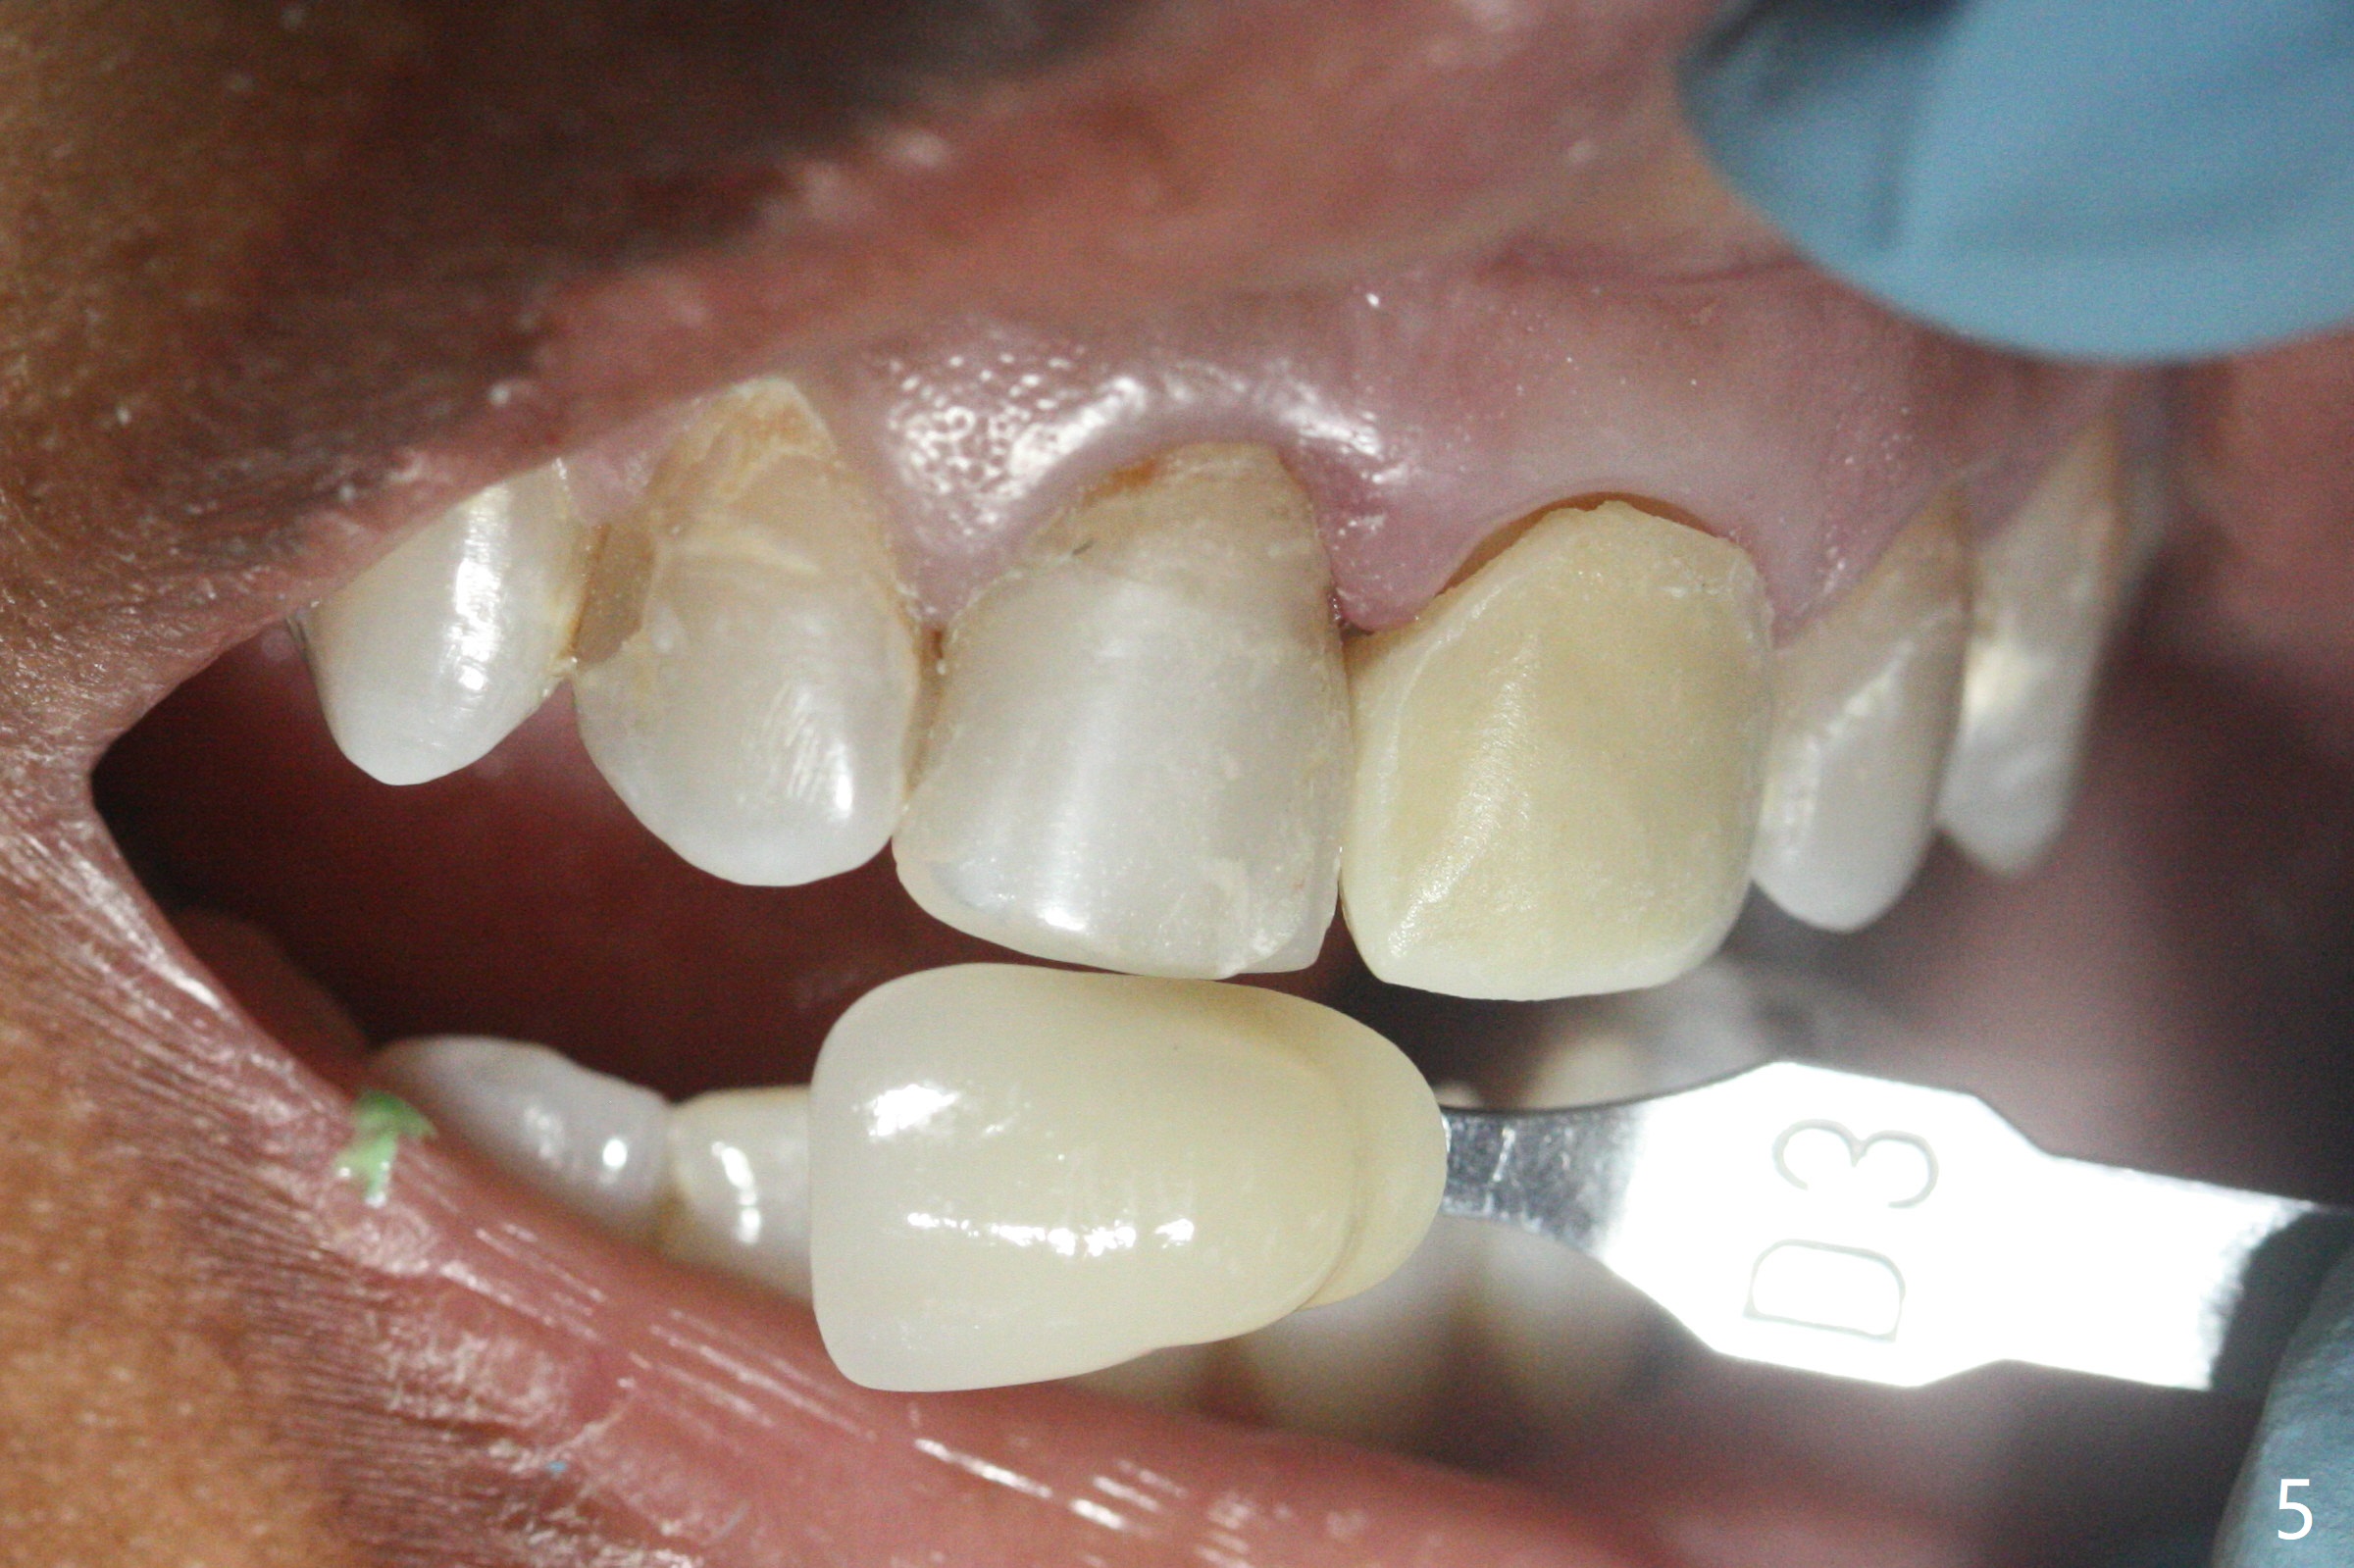

36岁女,9号牙树脂修补多次(图一),最近对冷热敏感,计划牙冠制备(如果不再敏感,再约一次与8号牙一起制备取模;如果敏感,9号牙根管治疗),使用Polycarbonate

Crown(图二,三)和Bosworth Trim II (Temporary Resin Acrylic

(D3)做内衬里)做临时牙冠。由于前者显得黄,而病人牙齿灰,她突然不满意,后来我们把临时牙冠表面磨掉,用Temporary

Resin Acrylic (D3)做外衬里(图四,五),勉强过关。大家如何处理这个难题?能买到类似Omnichrome树脂(composite)临时牙冠外壳?反映下面牙齿颜色。海平:临时牙冠facial